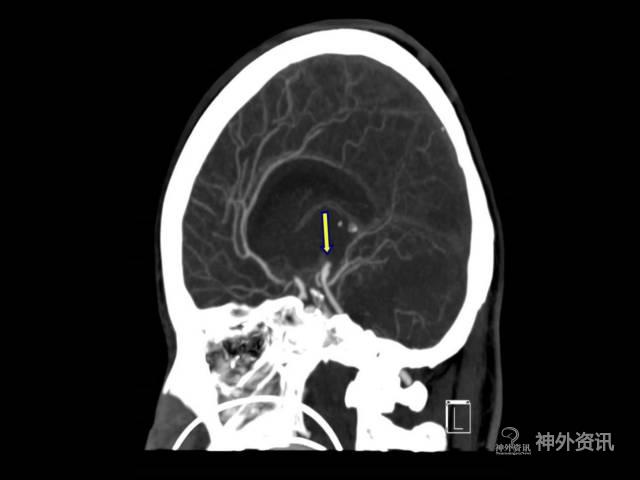

例如对于图18的未破裂大脑中动脉瘤,如果单纯从手术路径最近的角度分析,那么绿色箭头最近,可从绿色箭头上方所在位置精准打开侧裂,但是此例最终却选择了从黄色箭头相对较长的路径,也就是更靠向后方打开侧裂,因为从最终效果图21,可见瘤颈、载瘤动脉无遮挡,无论临时阻断还是夹闭都十分方便,而如果沿绿色箭头路径,最终效果为图20,可见在微小的侧裂暴露区,虽可勉强暴露瘤颈,但暴露载瘤动脉并置入临时阻断夹将十分困难,而且可能出现临时阻断夹和永久夹“打架”。

图18. 未破裂大脑中动脉瘤(绿色箭头路径侧裂开口更靠近前床突方向,黄色箭头路径侧裂开口更靠近后方)。

图19. 黄色箭头路径(更靠近后方),打开侧裂后的假想示意图,瘤颈载瘤动脉不受遮挡。

图20. 绿色色箭头路径(更靠近前床突方向),打开侧裂后的假想示意图,瘤颈载瘤动脉部分遮挡,有效操作空间小。

图21. 黄色箭头路径最终效果图。